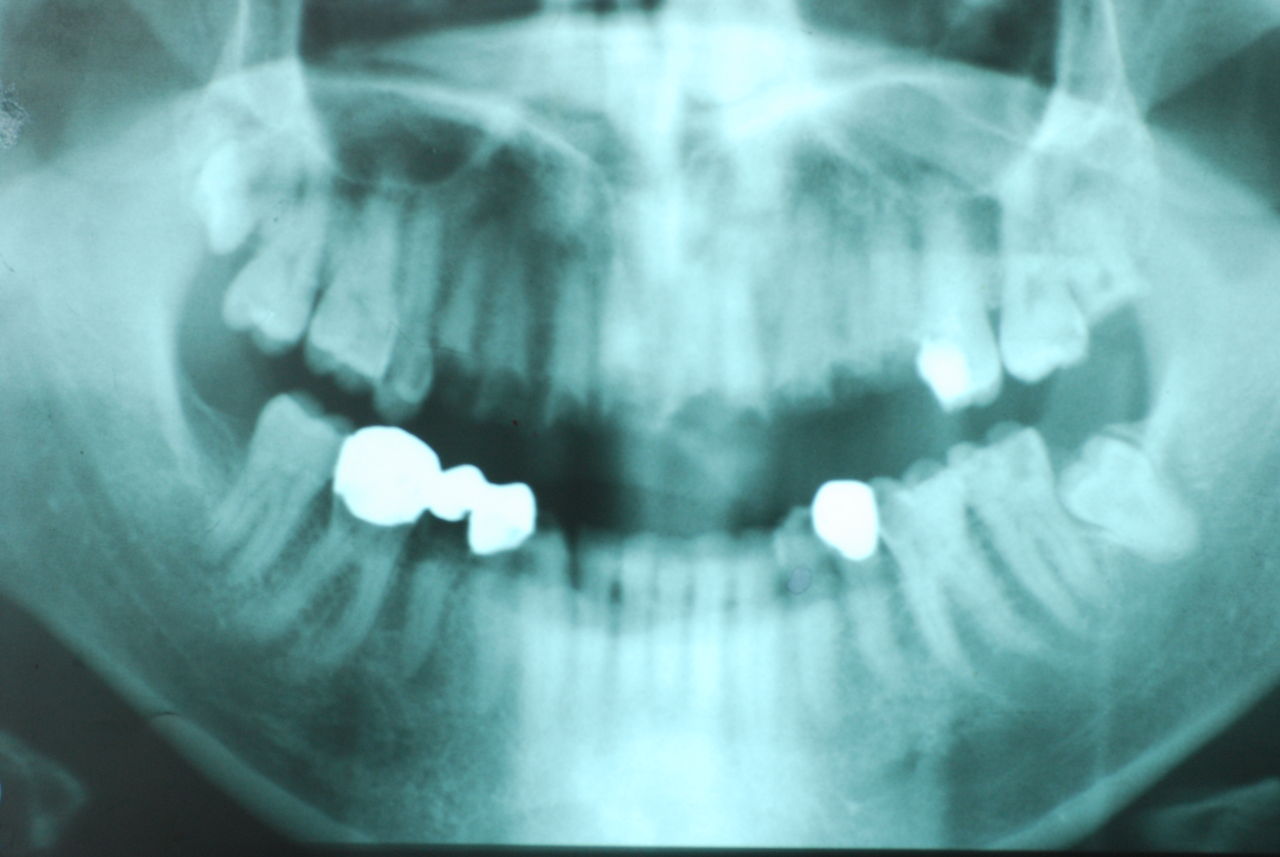

30代の男性の方です。

入れ歯を入れていました。歯科医院で歯を抜けず仕方なく入れ歯にしたとか。何とかならないものだったのか悔やまれました。

抜いた歯はありません。

一応差し歯にしましたが、歯茎の状態はよくはありません。

とりあえず希望を入れて差し歯にしたような感じです。